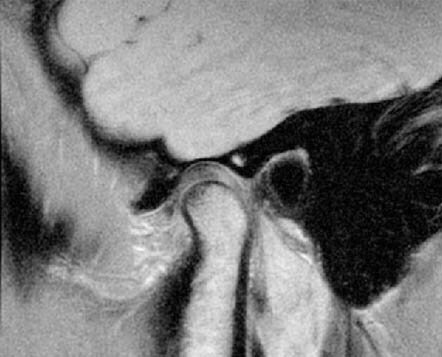

Аксиография — это компьютерное диагностическое исследование, регистрирующее движения нижней челюсти.

Аксиография — это компьютерное диагностическое исследование, регистрирующее движения нижней челюсти. Прибор, с помощью которого выполняется исследование, называется электронный аксиограф. Данные, полученные в ходе исследования, переводятся на компьютер, анализируются и в дальнейшем служат критерием для настройки артикулятора.